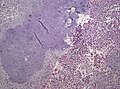

Ependymoma grade II WHO. H&E stain

LM Perivascular pseudorosettes, ependymal rosettes

"Classic" ependymoma

• Come in two CNS WHO grades: 2 and 3.

• Usu. sharply demarcated from surrounding brain parenchyma.

Features:

• Cells have a "tadpole-like" morphology.

• May also be described as ice cream cone-shaped.[5]

• Rosettes = circular nuclear free zones/cells arranged in a pseudoglandular fashion; comes in two flavours in ependymoma:

• Perivascular pseudorosettes = (tumour) cells arranged around a blood vessel; nuclei of cells distant from the blood vessel, i.e. rim of cytoplasm (from tumour cells) surround blood vessel (nucleus-free zone); more common than ependymal rosette... but less specific.

• Ependymal rosette (AKA true ependymal rosette) = rosette has an empty space at the centre - key feature.

• Nuclear features monotonous, i.e. "boring".[6]

• There is little variation in size, shape and staining.

• Hyalinized vessels.

• Calcification.